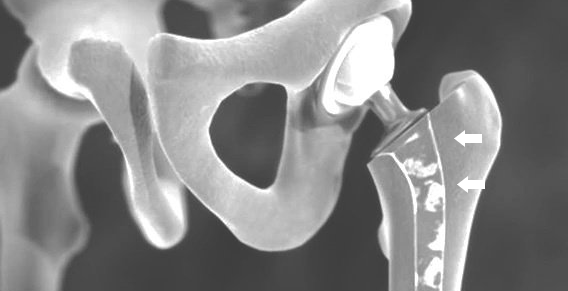

IN PARTICULAR, INFECTION of the prosthesis material, EARLY POST-COLLAPSITING OF THE Shaft or a fracture of the bone involving the implants are feared as complications in the HIP JOINT.

When replacing the prosthesis, re-operation can often be performed with a primary hip implant. Sometimes special revision implants are also necessary.